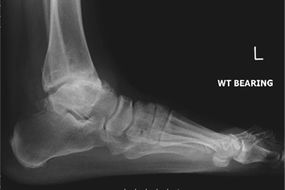

- „Hinterer“ Fersensporn / Insertionstendinopathie:

- ist eine Verschleißerkrankung des Achillessehnenansatzes am Fersenbein. Sie ist meist bedingt durch Überlastung und deshalb häufig bei Sportlern zu finden. Meist besteht eine knöcherne Verdickung der hinteren Ferse, die sich auch immer wieder – v.a. durch Reibung in geschlossenen Schuhen – entzünden kann. Im Ultraschall kann die Diagnose schnell gesichert werden, im Röntgenbild wird das komplette Ausmaß der knöchernen Spornbildung sichtbar.